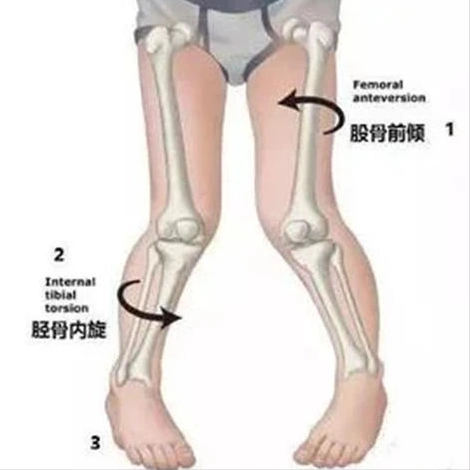

的腿骨发育带来巨大的伤害,也是这个孩子走路为什么内八的重要原因

孩子突然跛行,走路姿势突然有时点不对劲,脚尖往里撇,不哭,不闹,不喊